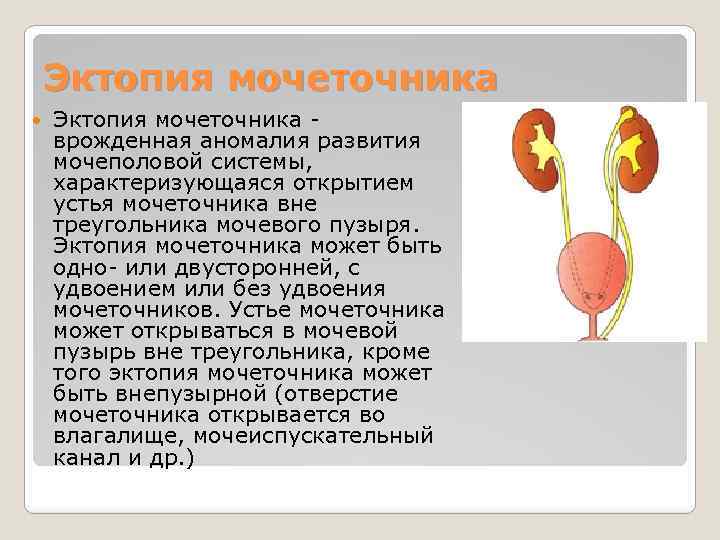

Эктопия мочеточника врожденная аномалия развития мочеполовой системы, характеризующаяся открытием устья мочеточника вне треугольника мочевого пузыря. Эктопия мочеточника может быть одно- или двусторонней, с удвоением или без удвоения мочеточников. Устье мочеточника может открываться в мочевой пузырь вне треугольника, кроме того эктопия мочеточника может быть внепузырной (отверстие мочеточника открывается во влагалище, мочеиспускательный канал и др. )

Эктопия мочеточника врожденная аномалия развития мочеполовой системы, характеризующаяся открытием устья мочеточника вне треугольника мочевого пузыря. Эктопия мочеточника может быть одно- или двусторонней, с удвоением или без удвоения мочеточников. Устье мочеточника может открываться в мочевой пузырь вне треугольника, кроме того эктопия мочеточника может быть внепузырной (отверстие мочеточника открывается во влагалище, мочеиспускательный канал и др. )